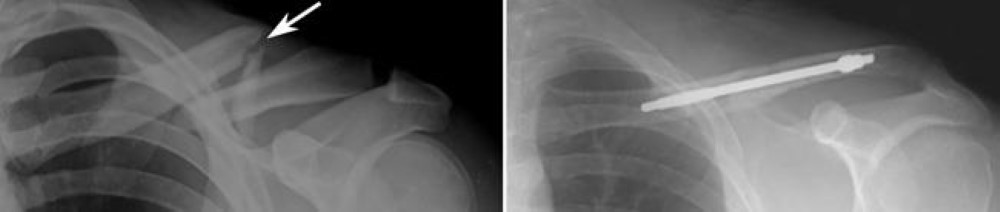

Internal fixation of clavicle fracture

(Left) X-ray shows a displaced clavicle fracture (arrow). (Right) The pieces of bone have been realigned and held in place with plates and screws.

Images courtesy of Stuart J. Fischer, MD, FAAOS